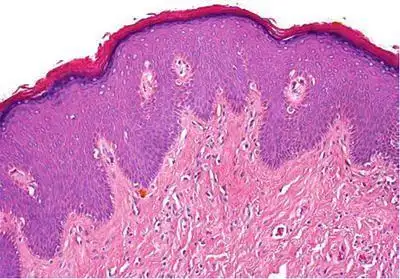

外阴鳞状上皮细胞增生